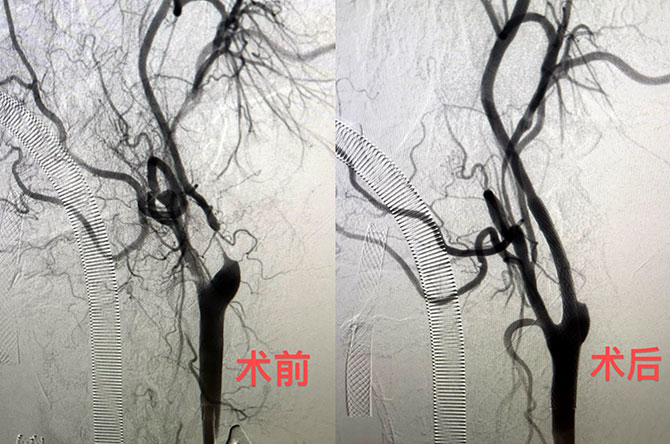

日前,神经外科在完成各种复杂颈动脉内膜剥脱等颈部血管性疾病手术的基础上,再创新高,陈光忠主任医师、秦琨副主任医师联合神经内科代成波主任团队,在神经电生理室、麻醉科和手术室等兄弟科室的支持下,成功开展颈动脉狭窄治疗的全新术式:经颈动脉血运重建术(TCAR)。术后患者康复顺利。

颈动脉狭窄是引起脑卒中的重要原因之一。药物治疗是基础,颈动脉内膜剥脱(CEA)和颈动脉支架成形术(CAS)是传统上治疗颈动脉狭窄的两种手术方式。CEA存在神经损伤、长时间阻断血流等不足。CAS即使在保护伞保护状态下仍有一定比率的栓塞发生,且需通过主动脉弓操作,受路径血管影响。

TCAR是一种新的、结合CEA和CAS两种治疗方法优势的颈动脉介入治疗方法,将颈动脉显露与血流逆转相结合,以最大程度减少栓塞发生的可能性。具有小伤口、微创、不经过主动脉弓、不接触斑块;同时,避开颅神经损伤,以及逆向血流保护和更低的心肌梗死、脑梗死发生率等优势,30天围手术期总卒中发生率低至1.4%,让颈动脉狭窄的治疗更加安全有效。